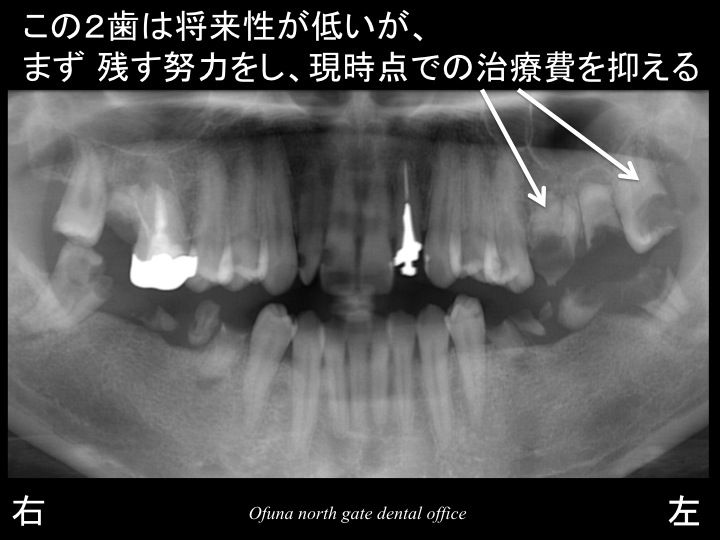

以下は初診時のレントゲンです。

いつも見ている方には みなれたことと思います。

始めて見られる方のために 簡単に以下のレントゲンの見方

について説明します。

以下のレントゲンの下に 右、左と書いてありますが、

当然のことながら 右と書いてあるのが“ 右側 ”です。

実際の左右とは違いますので、今後見られる時にはご注意下さい。

虫歯がいっぱいあることが分かるかと思います。

このように多くの虫歯がある方がいらっしゃいます。

また、以下の歯も抜歯ではありませんが、将来性は低い歯と言えます。

本当に多くの歯に問題があります。